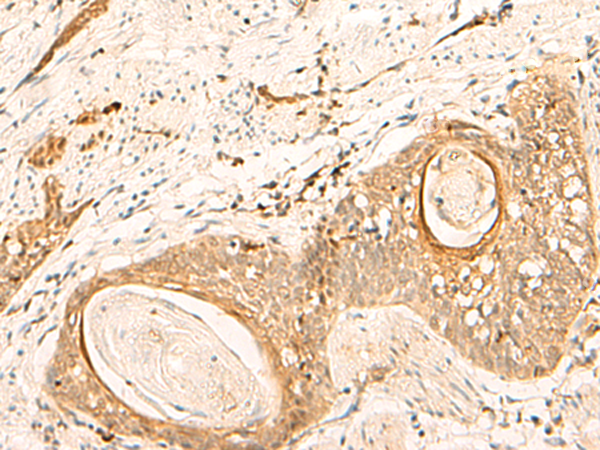

(The image is immunohistochemistry of paraffin-embedded Human esophagus cancer tissue using 47321(EIF3C Antibody) at dilution 1/35.(Original magnification: 200))

(The image is immunohistochemistry of paraffin-embedded Human tonsil tissue using 47321(EIF3C Antibody) at dilution 1/35.(Original magnification: 200))